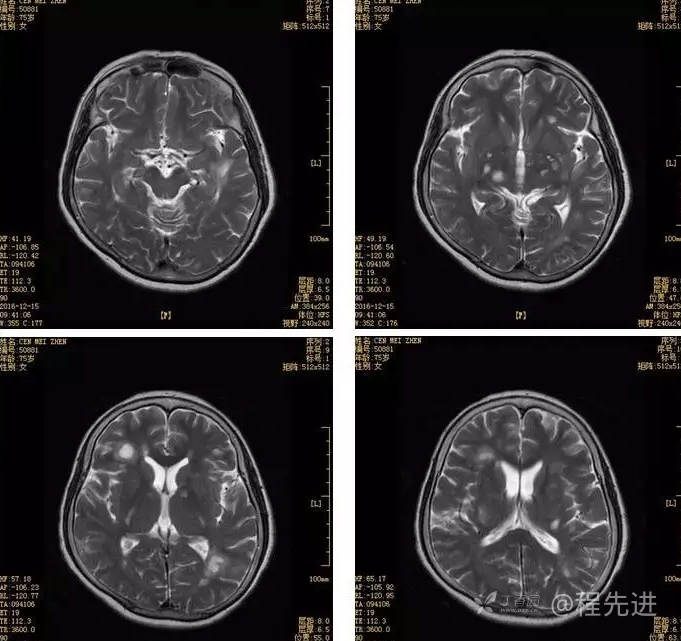

3月特别精彩病例|头晕伴左侧肢体乏力、行走不稳1周【结果已公布】

患者性别:女

患者年龄:75岁

简要病史:头晕伴左侧肢体乏力、行走不稳1周。否认高血压、脑梗塞、肝炎、糖尿病、肺结核病史。否认疫区疫水接触史。